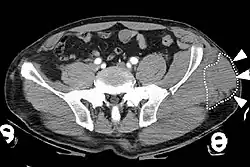

Computed tomography

Computed tomography (CT) is important in settings of an emergency or when magnetic resonance imaging is not available.[8] CT will show the presence of a Morel-Lavallée lesion and whether fluid is present.[7] The use of contrast can also help determine if fluid present in a lesion is due to active bleeding.[8]